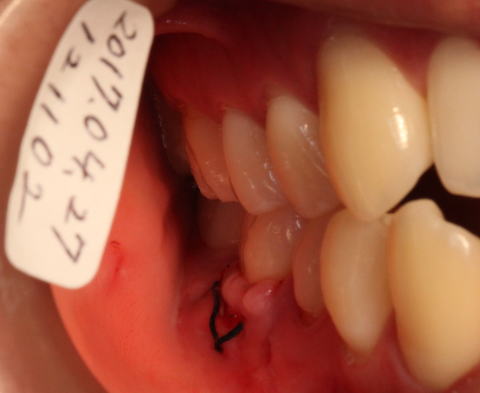

2017-04-27 術後1週間後です。 歯ぐきの形がいびつです。 |

2017-05-06 j術後約2週間後です。 抜糸をしました。 歯ぐきの形はまだいびつです。 |